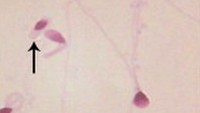

Sperma ini memiliki abnormalitas kepala yang terlalu bulat. (Foto: Middle East Fertility Society Journal/Sohair A. Abd El-baset)